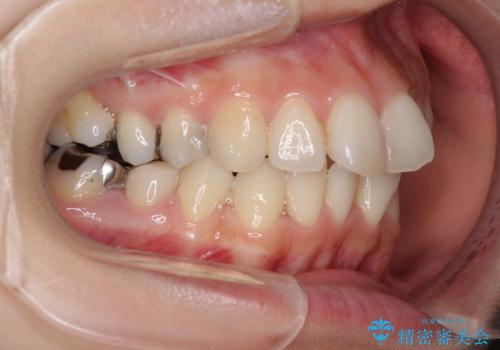

- 上下のデコボコと奥歯の咬みにくさを気にして来院された患者様です。

上顎骨の幅が下顎骨よりも小さいので、拡大装置により骨幅を広げて上下関係を改善し、その後インビザラインにて歯並びを整えることとしました。

上下の骨幅を改善したことで、スムーズに歯列矯正を行うことができました。

矯正治療中に近医で銀歯を外す治療を開始したため、治療後に奥歯の咬み合わせが不十分ですが(こちらは近医での治療により改善するとのこと)、歯列と咬み合わせが改善され、患者様には大変満足していただきました。